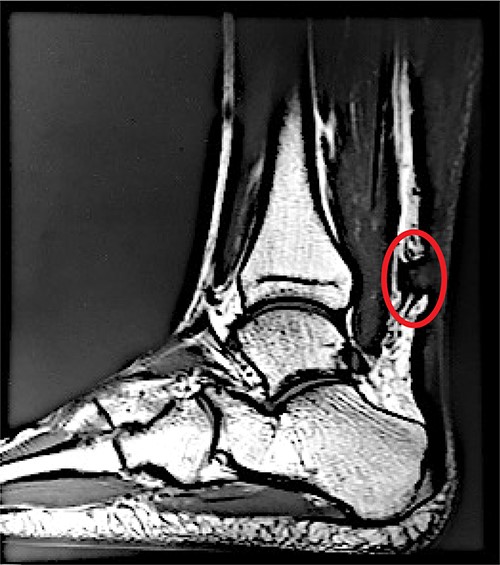

A sagittal view of the MRI of patient’s left Achilles demonstrates an acute, complete, Achilles rupture (circled in red) ~4 cm above the calcaneal insertion.

On physical examination, a notable gap defect over the midsubstance of the left Achilles tendon was noted with swelling and edema of the left ankle. The patient also had loss of plantar flexion tone on the affected side as well as a positive Thompson test. He was neurovascularly intact with strong perfusion noted distally with palpable dorsalis pedis pulses. Radiographic confirmation with a magnetic resonance imaging (MRI) demonstrated a full-thickness tear of the left Achilles tendon 4 cm above the calcaneal insertion (Fig. 1). After extensive discussion regarding risks and benefits, a decision was made to undergo operative repair of this injury. Exactly 1-week post-injury, the patient underwent open primary repair of the left Achilles tendon without any complications (Fig. 2). In the immediate post-operative period, the patient was placed in a hard, immobile cast with plantar flexion that was then removed at post-operative day (POD) 14. After removal of the cast, the patient was started on an early functional rehabilitation program and in a functional brace for 6 weeks before transitioning to normal footwear. At POD 14, tension offloading therapy was begun on the inferior portion of the incision and was utilized daily until POD 120. The superior portion of the incision was left untreated for comparison. At POD 120, the tension offloading was discontinued (Fig. 3).